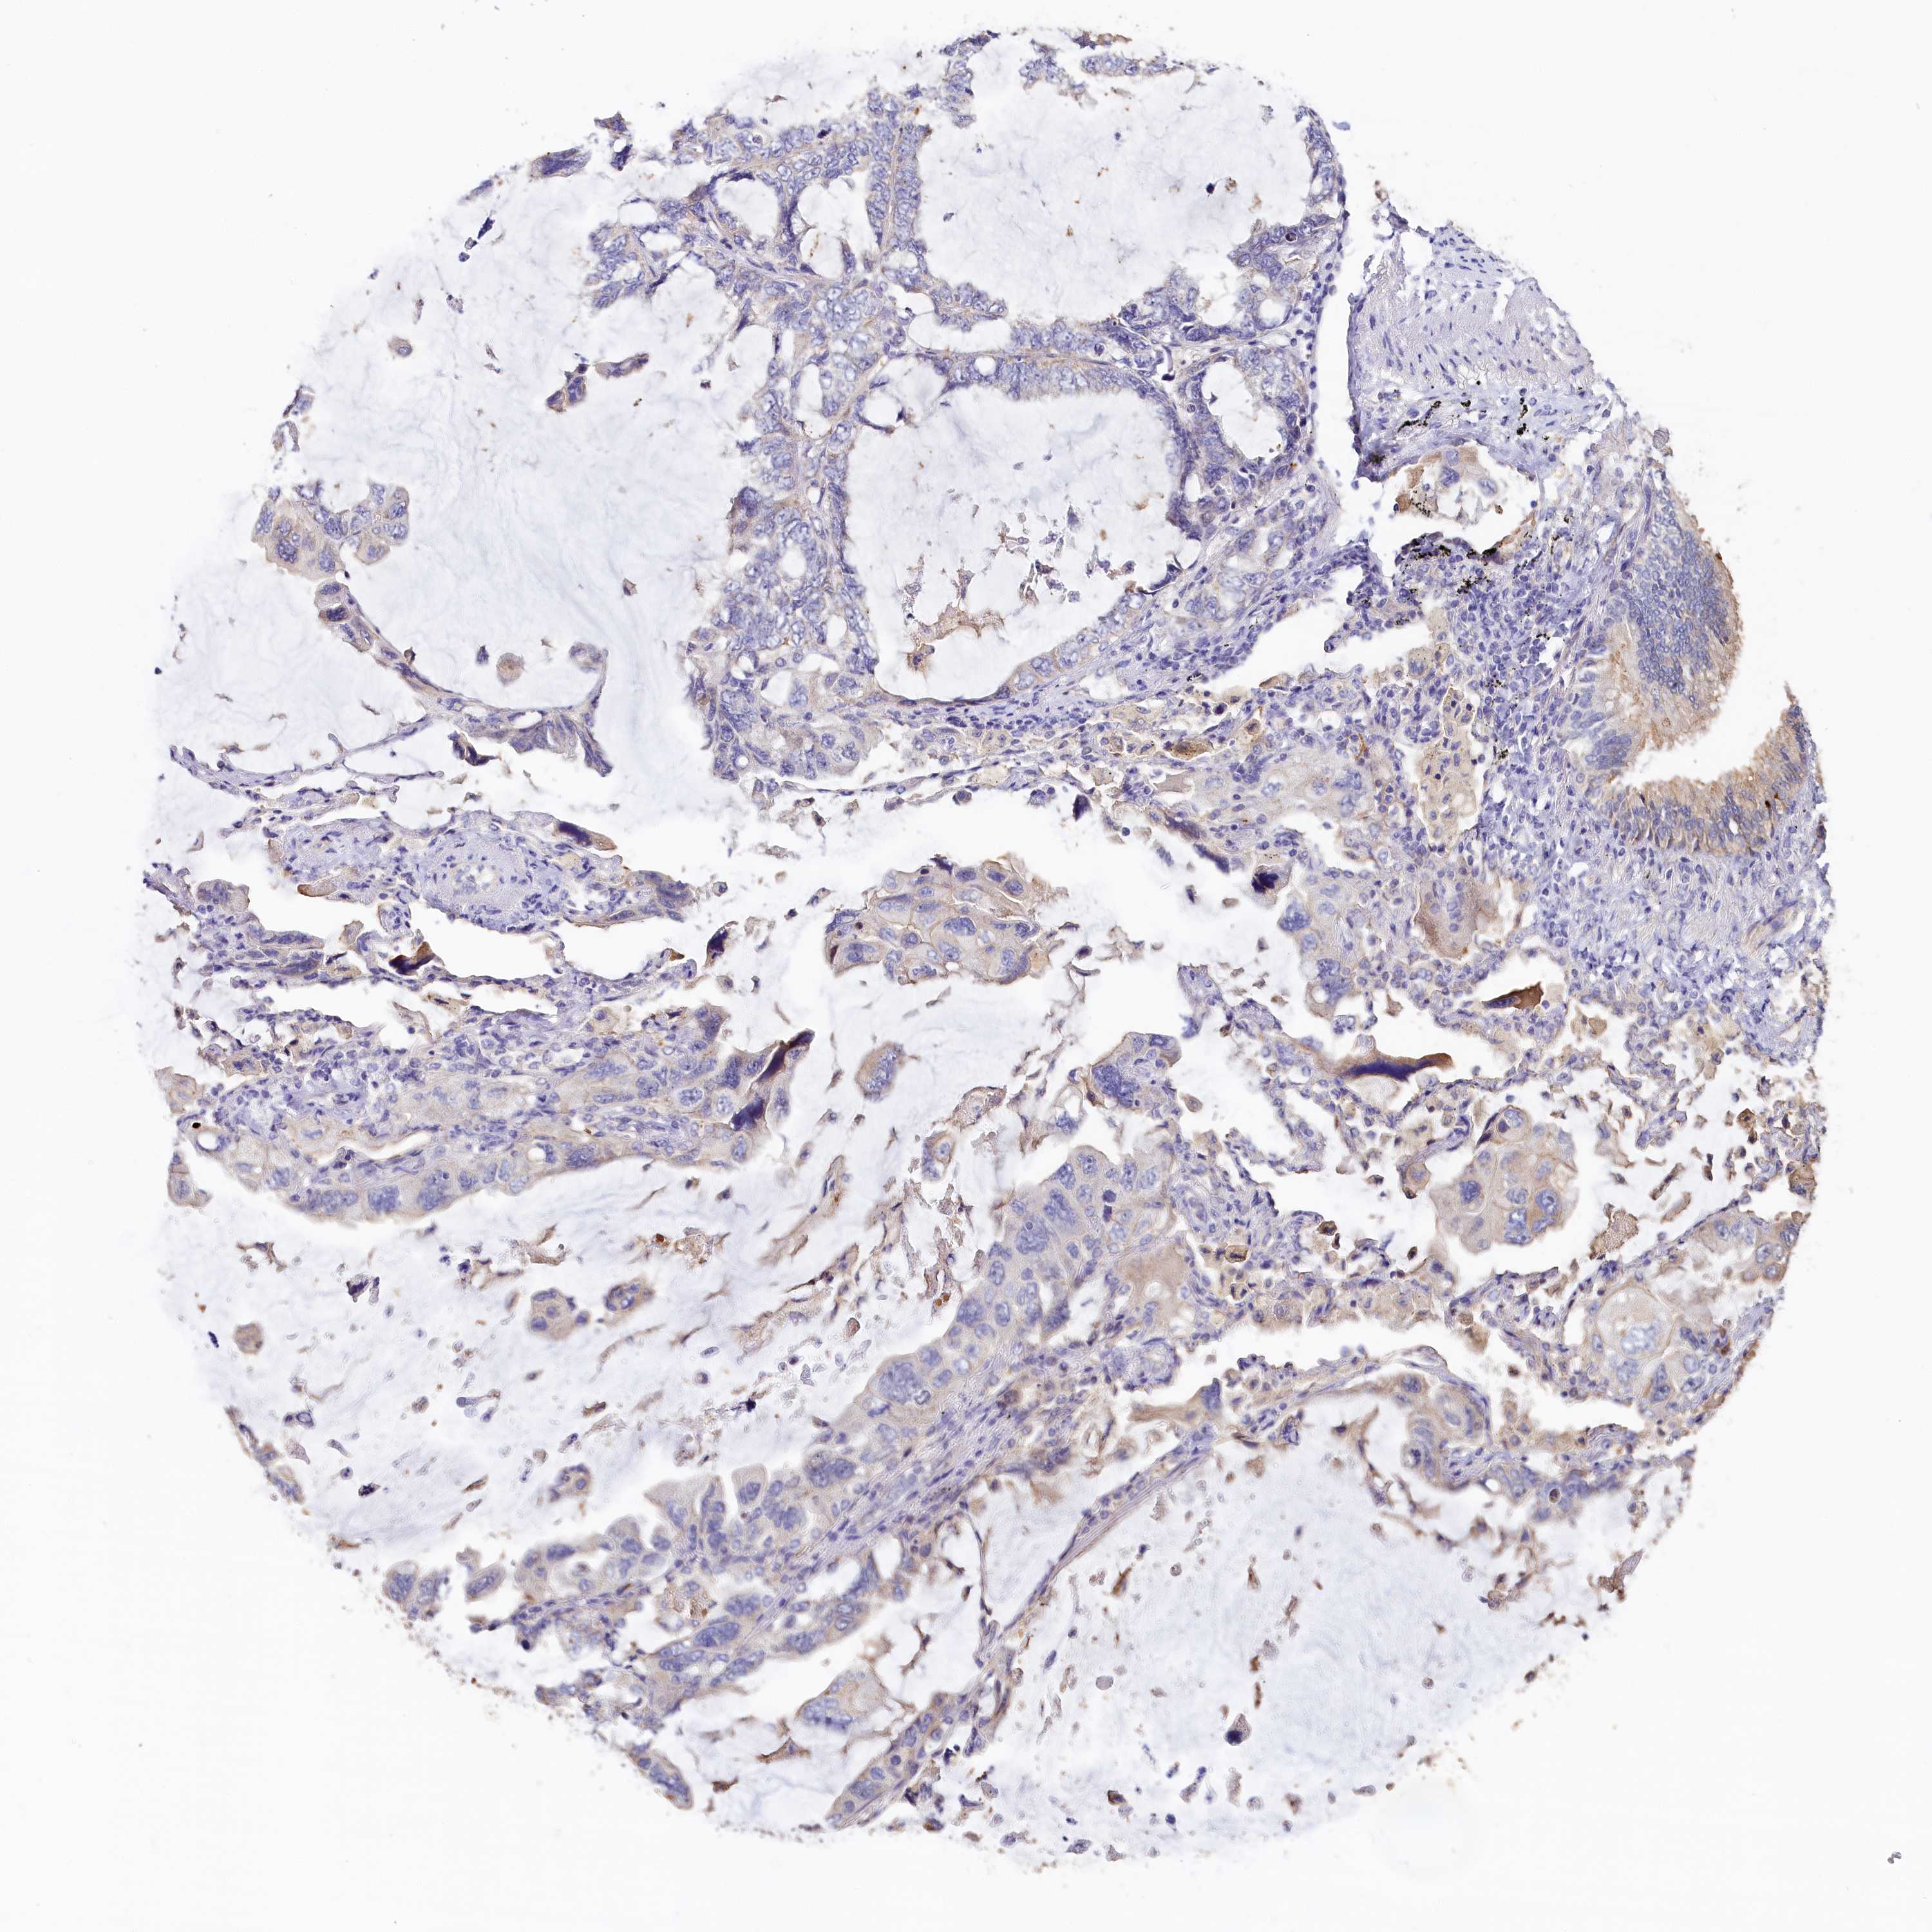

LUNG ADENOCARCINOMA (TCGA) - Interactive survival scatter ploti

The Survival Scatter plot shows the clinical status (i.e. dead or alive) for all individuals in the patient cohort, based on the same data that underlies the corresponding Kaplan-Meier plots. Patients that are alive at last time for follow-up are shown in blue and patients who have died during the study are shown in red.

The x-axis shows the expression levels (FPKM) of the investigated gene in the tumor tissue at the time of diagnosis. The y-axis shows the follow-up time after diagnosis (years). Both axes are complimented with kernel density curves demonstrating the data density over the axes. The top density plot shows the expression levels (FPKM) distribution among dead (red) and alive patients (blue). The right density plot shows the data density of the survived years of dead patients with high and low expression levels respectively, stratified using the cutoff indicated by the vertical dashed line through the Survival Scatter plot. This cutoff is automatically defined based on the FPKM cutoff that minimizes the p-score. The cutoff can be changed by dragging the vertical line or by entering a cutoff value in the square labeled "Current cut-off".

Under the Survival Scatter plot the p-score landscape (black curve; left axis) is shown together with dead median separation (red curve; right axis). Dead median separation is the difference in median mRNA expression between patients who have died with high and low expression, respectively. It is calculated as follows: median FPKM expression of dead patients with high expression - median FPKM expression of dead patients with low expression. This is intended to aid the user in visually exploring custom cutoffs and the associated p-scores and dead median separation.

Individual patient data is displayed and can be filtered by clicking on one or more of the category buttons on the top of the page. Categories describing expression level and patient information include: high, low, alive, dead, female, male and tumor stages. The scale of the x-axis can be toggled between linear and log-scale by clicking on the "x log" button. Mouse-over function shows TCGA ID, patient information and mRNA expression (FPKM) for each patient.

& Survival analysisi

Kaplan-Meier plots summarize results from analysis of correlation between mRNA expression level and patient survival. Patients were divided based on level of expression into one of the two groups "low" (under cut off) or "high" (over cut off). X-axis shows time for survival (years) and y-axis shows the probability of survival, where 1.0 corresponds to 100 percent.

KATNB1 is not prognostic in Lung Adenocarcinoma (TCGA)

: 18.88

Average pTPM 17.4

Number of samples 497